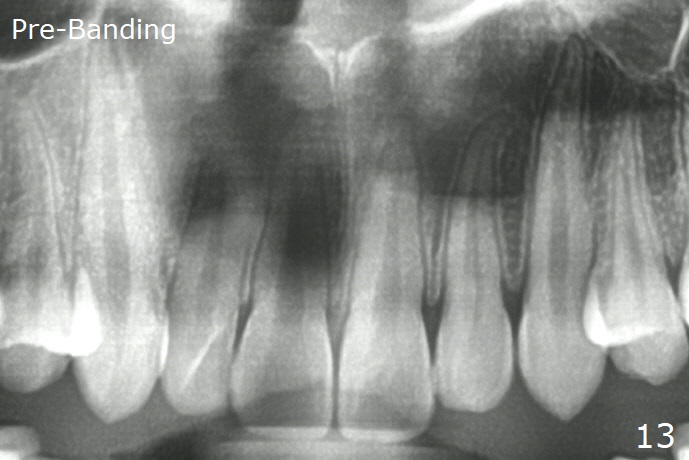

Anterior overbite and overjet and posterior interdigitation are satisfactory, while the roots of the upper incisors look shortened 23 months post banding (Fig.11,12, as compared to pre-banding (Fig.13). Brackets and bands are removed.